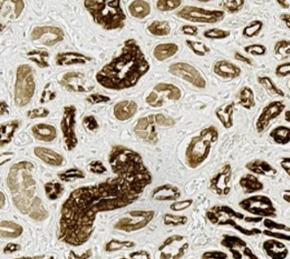

Species-On-Species

Detection of antigens in the same species of tissue can pose problems like high background staining and cross-reactivity.

Successful IF starts with specific, sensitive detection of target antigens with primary antibodies, but not all antibodies are up to the task.

Their portfolio of antibodies includes recombinant monoclonal antibodies for ensured lot-to-lot reproducibility,

antibodies validated for performance in 20+ tissue types, and highly-affinity goat polyclonal antibodies for sensitive detection of low-abundance targets.